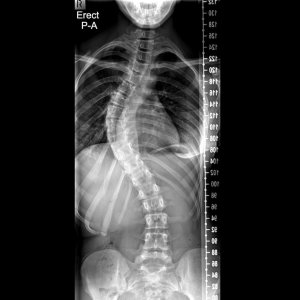

Scoliosis is a condition that causes the spine to curve sideways, instead of having a straight and vertical alignment. This can occur in any part of the spine, but most commonly affects the upper back (thoracic spine) or the lower back (lumbar spine). The curvature can range from mild to severe and can cause physical and emotional discomfort for those affected.